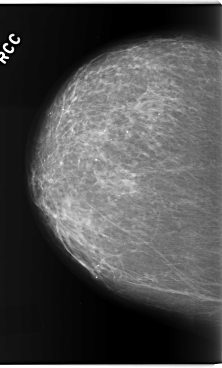

C_0205_1.RIGHT_CC

RIGHT_CC LINES 5888 PIXELS_PER_LINE 3552 BITS_PER_PIXEL 12 RESOLUTION 50 NON_OVERLAY